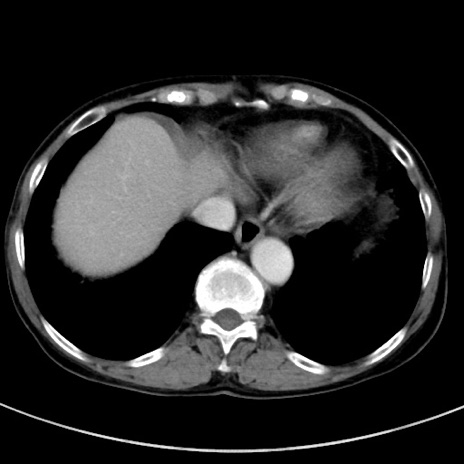

冠状断像